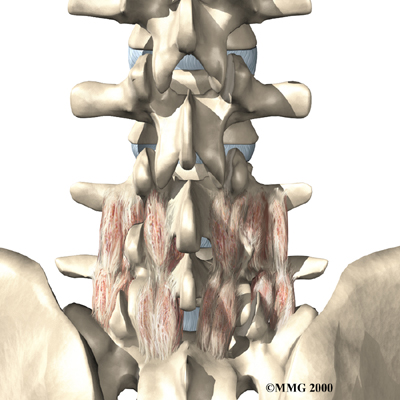

The next part of our program will include a series of strengthening exercises for the abdominal and low back muscles. Working these core muscles helps our patients begin moving easier and lessens the chances of future pain and problems. Aerobic exercises such as walking or swimming are used for easing pain and improving endurance.